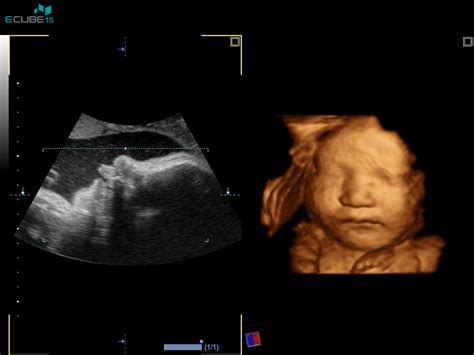

Ko opravite prve nosečniške preiskave, je v 12. tednu nosečnosti čas za ključna presejalna testa. Merjenje nuhalne svetline je ultrazvočna preiskava, ki se opravi med 11. in 14. tednom nosečnosti. Ginekolog s pomočjo ultrazvoka izmeri prosojni (tekočinski) predel za tilnikom ploda - to je t. i. nuhalna svetlina. Zakaj je to pomembno? Ker povečana nuhalna svetlina lahko nakazuje na povečano tveganje za kromosomske napake, kot je na primer Downov sindrom (trisomija kromosoma 21), Edwardslov sindrom (trisomija kromosoma 18) ali Patauov sindrom (trisomija kromosoma 13). Pomembno je poudariti, da gre za presejalni test, kar pomeni, da ne postavlja diagnoze, ampak le oceni verjetnost za določene nepravilnosti.

Ob istem času ali nekoliko prej se običajno opravi tudi dvojni hormonski test (DHT). Ta test meri vrednosti dveh hormonov v materinem serumu: nosečniškega hormona hCG (humani horionski gonadotropin) in hormona PAPP-A (nosečnostno povezan plazemski protein A). Količine teh hormonov se lahko pri nekaterih kromosomskih napakah (npr. pri Downovem sindromu) znatno razlikujejo od normalnih vrednosti. Ta test običajno opravite istega dne kot ultrazvok z meritvijo nuhalne svetline, lahko pa se vzorec krvi za dvojni hormonski test odvzame že prej. Kar je pomembno, je to, da se rezultati obeh preiskav interpretirajo skupaj. Na podlagi starosti nosečnice, izmerjene nuhalne svetline in drugih podatkov UZ preiskav ter vrednosti omenjenih hormonov, računalniški program izračuna individualno tveganje za kromosomske nepravilnosti kromosomov 13, 18 in 21. Če vaš izbrani ginekolog teh storitev ne izvaja, lahko oboje opravite tudi v naši ambulanti.

Prenatalna genetska diagnostika je indicirana po pozitivnem NIPT, pozitivni družinski anamnezi, pozitivnih presejalnih testih iz materinega seruma ali patološkem UZ. Invazivna prenatalna diagnostika se izvaja v 12. tednu nosečnosti po biopsiji horionskih resic ali v 16. - 18. tednu po amniocentezi.